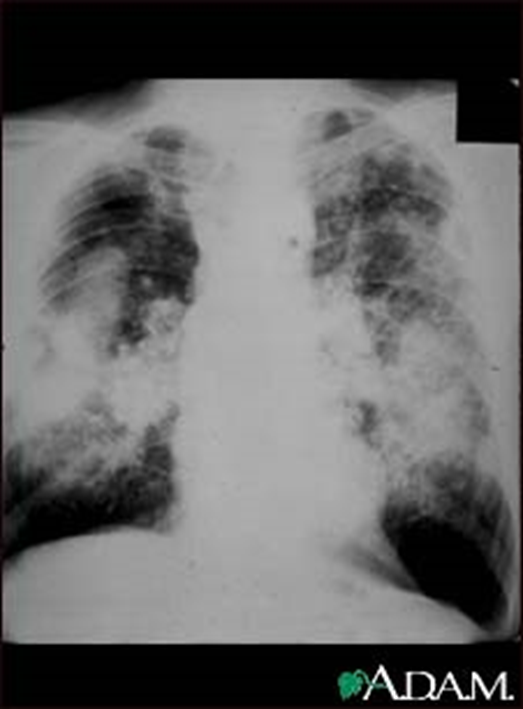

3)大阴影:是晚期矽肺和煤矽肺的重要X线表现,呈椭圆形、长梭形或不规则形,边缘清晰,周边肺气肿明显。大阴影多是由小阴影增大、密集、融合而形成;也可由少量斑片、条索状阴影逐渐相连并融合呈条带状。周边肺气肿比较明显,形成边缘清楚、密度较浓、均匀一致的大阴影。多在两肺上、中区出现,左右对称。煤肺患者晚期罕见大阴影。

complicated coal workers pneumoconiosis complicated coal workers pneumoconiosis

此外,煤工尘肺的肺气肿多为弥慢性、局限性和泡性肺气肿。泡性肺气肿表现为成堆小泡状阴影,直径为1~5mm,即所谓“白圈黑点”。晚期可见肺大泡。

此外,煤工尘肺可见到肺纹理增多、增粗、扭曲变形,肺门阴影增大、密度增高,还可见到淋巴结蛋壳样钙化或桑椹样钙化阴影,胸膜增厚、钙化改变者较少见,但常可见到肋膈角闭锁及粘连。